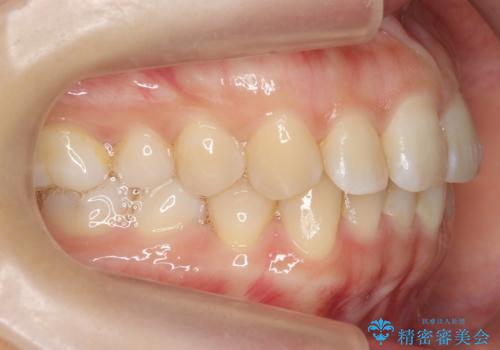

下の前歯のがたつき インビザラインで

- 前歯のがたつきを主訴に来院。

インビザラインで上下の前歯をわずかに削って並べました。